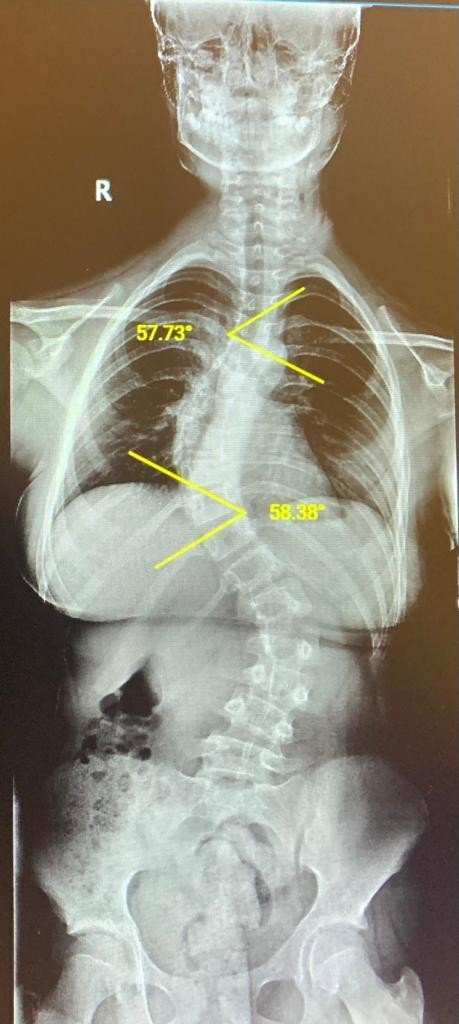

6'ıncı sınıf öğrencisi 12 yaşındaki Gökçe Uçar da zaman zaman sırtında ağrı yaşıyordu. Dönem dönem ağrıları şiddetlenen küçük kızın sırtında bir eğrilik olduğunu ilk ablası fark etti. Babası Aytaç Uçar ise, kızının yaz günü çok fazla bisiklet kullandığını, çoğunlukla da tek elle kullanmasından kaynaklı bir durum olabileceğini düşünse de yapılan tetkiklerde durum farklı çıktı. Gökçe'nin omurgası oldukça eğriydi. Skolyoz derecesi düşük olan kişilerde daha çok egzersiz ve korse ile takibinin yapıldığını belirten Medicana International İzmir Hastanesi Ortopedi ve Travmatoloji Uzmanı Doç. Dr. Mutlu Çobanoğlu, Gökçe'nin eğrilik derecesinin 60 derece olması nedeniyle ameliyat edilmesine karar verdi.

Gökçe'nin ameliyatını gerçekleştiren Ortopedi ve Travmatoloji Uzmanı Doç. Dr. Mutlu Çobanoğlu, hastanın yaşına göre farklı ameliyat teknikleri olduğunu ancak 10 yaşından önce omurgalara kaynaştırma ve dondurma da denilen füzyon ameliyatı yapmak istemediklerini belirterek, "Eğer hastalık erken dönemdeyse büyüme dostu yöntemleri tercih ederiz ancak artık büyüme potansiyeli azalmış ve yüksek skolyoz derecesi olan kişilerde füzyon tekniği evrensel bir yöntem. Biz de Gökçe'de bunu tercih ettik. Eğriliğin olduğu bölgedeki kemikleri kaynaştırıp tek kemik haline getiriyoruz. Kemik aşıları ile destekleyerek kemiklerin birbirine kaynamasını sağlıyoruz" diye konuştu.